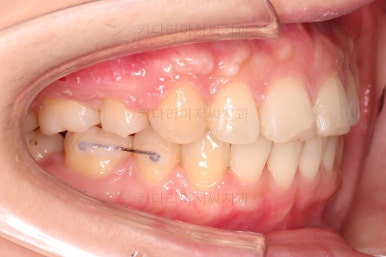

우선 장치를 부착해요.

환자분이 선택하신 장치는 엠파워 클리어라고 하는 자가결찰 세라믹 장치에요.

흔히들 클리피씨라고 많이 알고 계신 장치도 자가결찰 세라믹 장치의 한 종류에요.

제조사가 일본(클리피)이냐 미국(엠파워)이냐의 차이일 뿐이죠.

교정장치를 부착한 직후의 모습인데요.

눈에 보이는 장치의 모습과 입매의 변화를 참고해 주세요.

옆라인만 비교해보면요.

입매가 거의 변하지 않는 타입이세요.

교정장치 때문에 입이 많이 나올지, 안나올지는 사람마다 매우 달라서 말그대로 붙여봐야 아는 경우가 많습니다.

장치 부착 후에 순차적으로 4개의 치아를 발치해주고요.

치아를 뽑은 위치, 당겨야 할 정도가 달라 미니스크류를 몇 개 사용했어요.

미니스크류는 앞뒤조절, 높낮이 조절, 각도 조절, 안밖의 위치조절 등 난이도 높은 치료를 가능하게 해준답니다.